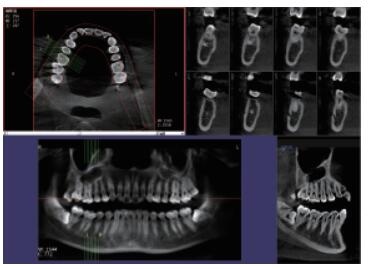

三維重建任意斷層

專有三維重建算法,可提供任意位置高清斷層影像。

高清口腔全景影像

通過三維容積影像,提取高清口腔全景影像。

多平面組合重建

可同時觀察軸向面、冠狀面和矢狀面圖像,方便臨床診斷。